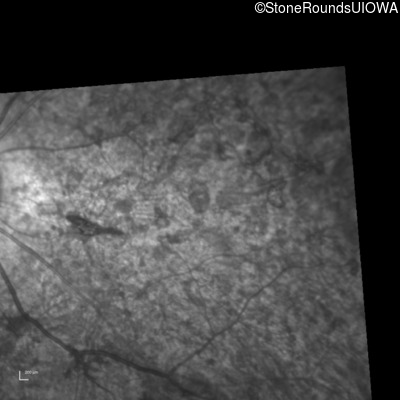

Infrared Fundus Photograph - Left - 20/250 sc

Exemplar